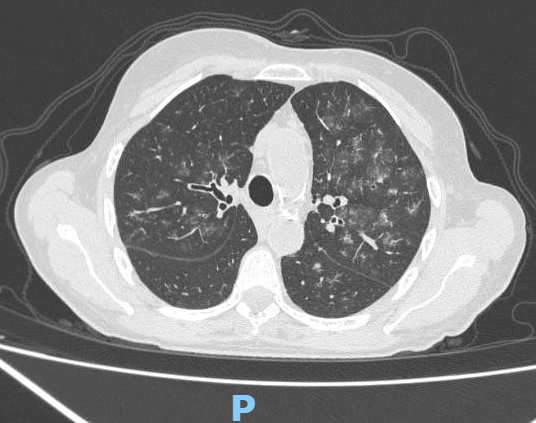

Radiografia de Tórax

TC de tórax sin contraste

Hemocultivos negativos. Urocultivo negativo. Lavado bronquialveolar sin rescates pero compatible con hemorragia alveolar.

Se interpretó una granulomatosis esosinofílica con poliangeítis (GEPA) con compromiso grave a nivel neurológico periférico y síndrome «pulmón-riñón» por compromiso pulmonar (hemorragia alveolar) y renal (proteinuria). Se indicó tratamiento inmunosupresor con dosis altas de esteroides e inducción de remisión con ciclofosfamida 1 g.